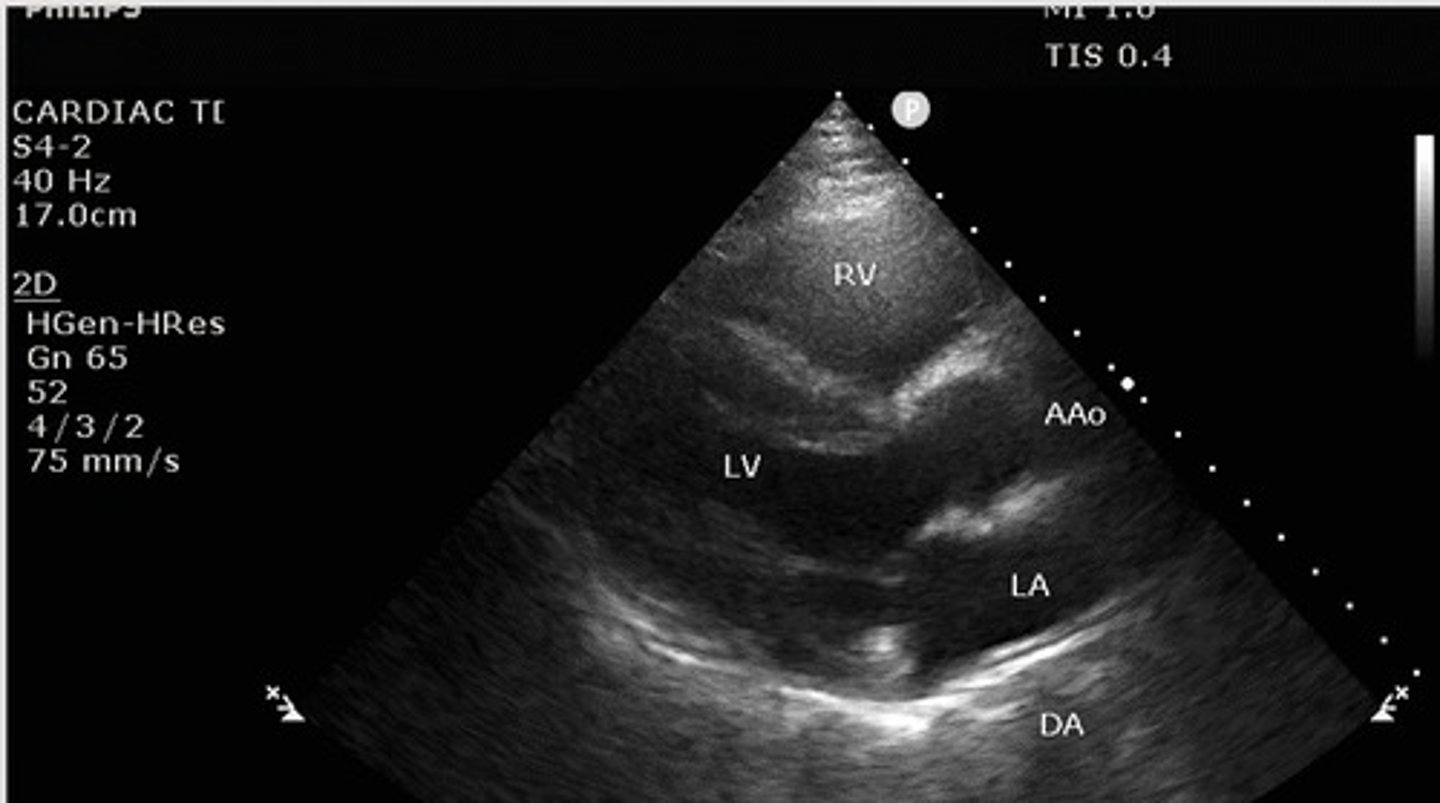

Parasternal long axis

What view of the heart is this?

what structures are seen with parasternal long axis view?